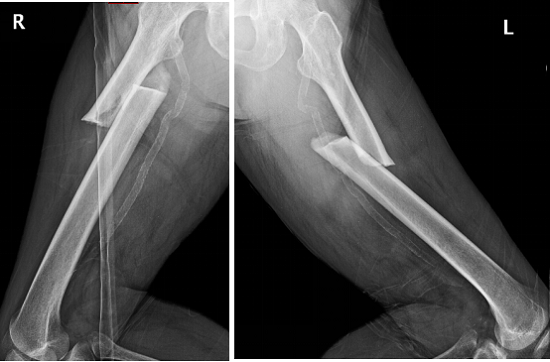

2018年上海交通大學醫學院附屬仁濟醫院創傷骨科碰到了一位從馬路臺階上摔倒的老年女性患者,拍片顯示是雙側股骨干近三分之一骨折(圖1),很對稱。

圖1